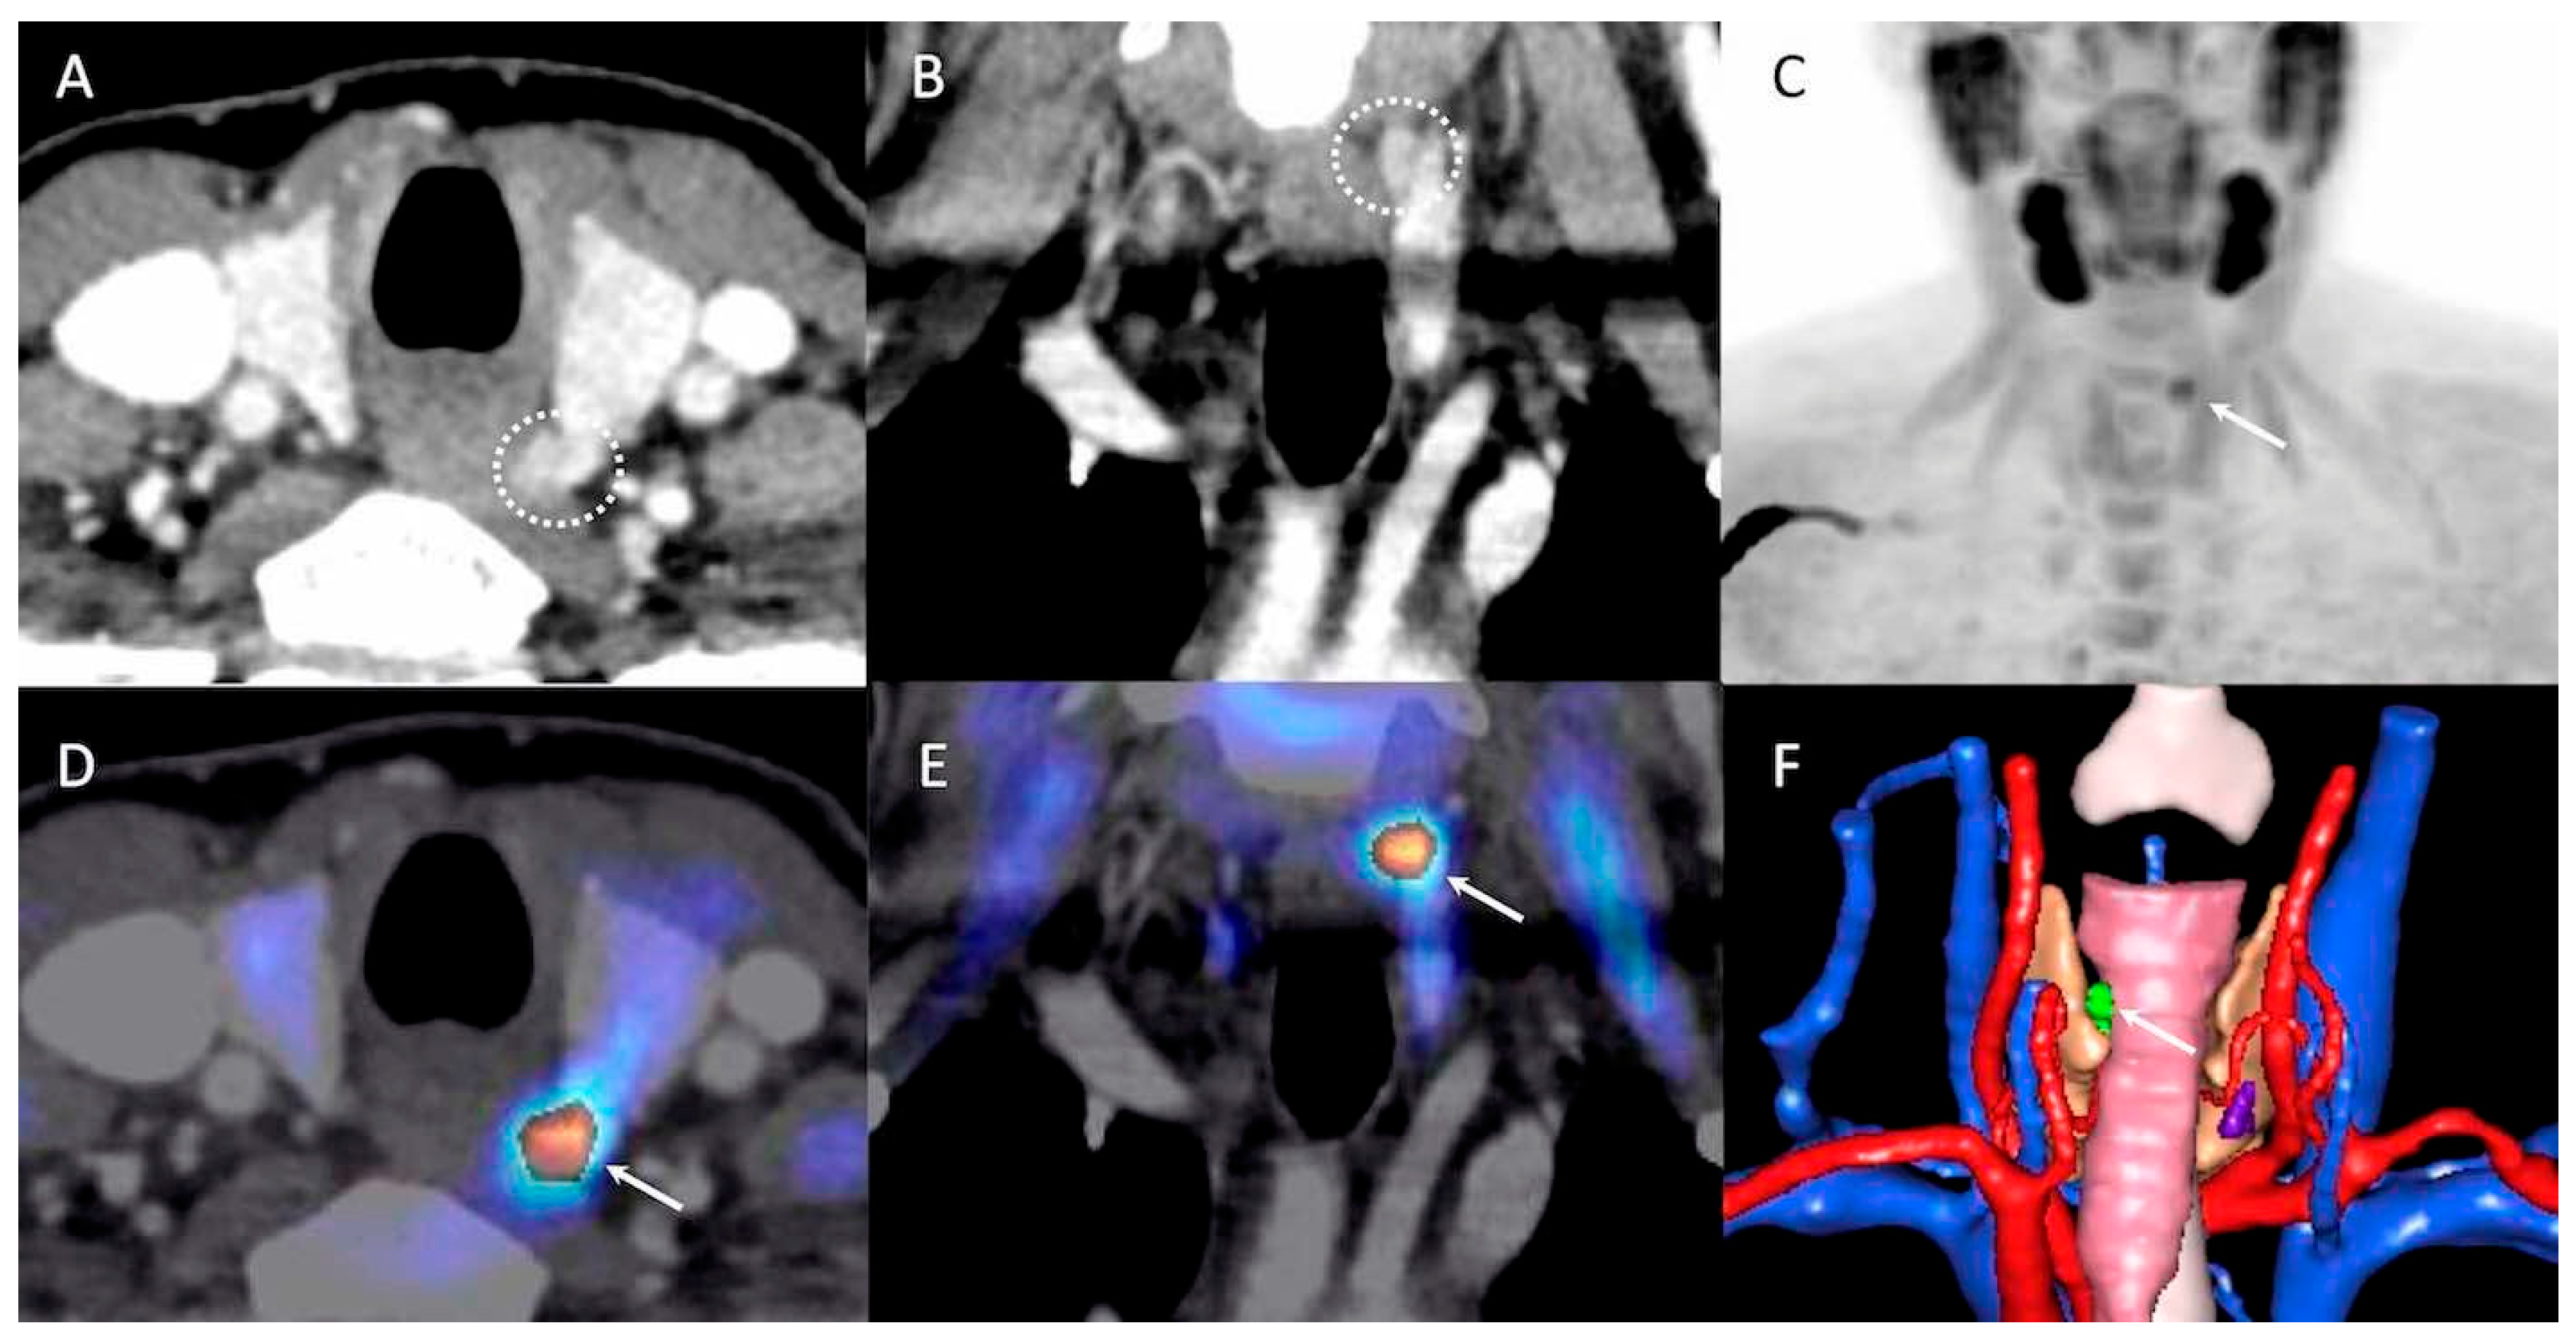

- Piccardo, A.; Trimboli, P.; Rutigliani, M.; Puntoni, M.; Foppiani, L.; Bacigalupo, L.; Crescenzi, A.; Bottoni, G.; Treglia, G.; Paparo, F.; et al. Additional value of integrated 18F-choline PET/4D contrast-enhanced CT in the localization of hyperfunctioning parathyroid glands and correlation with molecular profile. Eur. J. Nucl. Med. Mol. Imaging 2019, 46, 766–775. [Google Scholar] [CrossRef]

- D’Agostino, J.; Diana, M.; Vix, M.; Nicolau, S.; Soler, L.; Bourhala, K.; Hassler, S.; Wu, H.S.; Marescaux, J. Three-dimensional metabolic and radiologic gathered evaluation using VR-RENDER fusion: A novel tool to enhance accuracy in the localization of parathyroid adenomas. World J. Surg. 2013, 37, 1618–1625. [Google Scholar] [CrossRef] [PubMed]